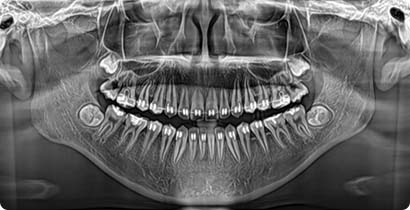

Digitális képalkotás

Teljes fogászati rendelő szoftver integrációja egyszerűen

A Fussen által nyújtott munkafolyamat-integrációja megkönnyíti és zökkenőmentessé teszi az adatátvitelt a rendelő minden helységétől a fogtechnikai laborig, megkönnyítve és gyorsabbá téve a klinikai eljárásokat.